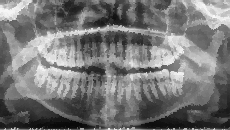

Diagnose